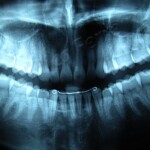

A princípio os procedimentos menores incluem as exodontias (extração de dentes) exodontias de dentes não irrompidos, ou que ao se desenvolverem não se acomodaram na arcada devido a falta de espaço, que neste caso é necessário um exame mais detalhado do caso, como radiografias, ou mesmo tomografias computadorizadas para um melhor diagnostico e planejamento cirúrgico.

A remoção de cistos do complexo maxilo-mandibular, que são lesões que se desenvolvem dentro do osso e o expandem, contendo líquido no seu interior, desencadeado por diversas causas.